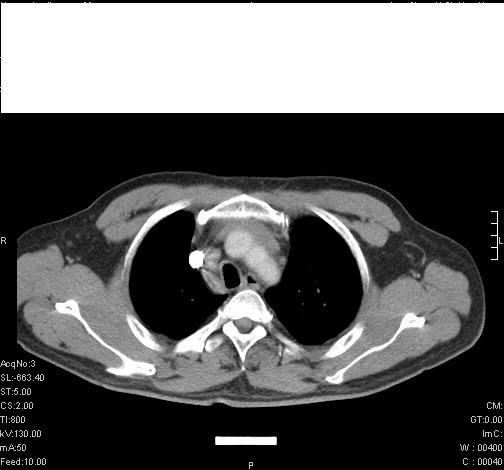

标题: CT6685:右肺阻塞性炎症,增强CT。 [打印本页]

标题: CT6685:右肺阻塞性炎症,增强CT。

前几天,发了患者的平扫片,患者抗炎一周后增强扫描。右中叶病灶吸收明显,但下叶病灶未见明显吸收。右肺门可见结节影,看来凶多吉少

右肺下叶支气管管腔狭窄,管壁增厚,右下肺见斑片状高密度影,考虑右侧肺门中心肺癌伴阻塞性肺炎

右肺下叶支气管壁明显增厚,考虑癌症并阻塞性炎症、肺门淋巴结肿大

考虑右肺癌并阻塞性炎症、肺门淋巴结肿大

右肺下叶支气管壁不规则增厚,右肺下叶有斑片状影分布。考虑右肺中央型肺癌伴右肺下叶阻塞性改变。建议支纤镜检查。平扫比增强较好显示了病变情况。

右主支气管狭窄,管壁增厚。考虑右中心性肺ca伴阻塞性肺炎。

既然抗炎治疗有效,可继续治疗;右肺下叶支气管管腔狭窄,管壁增厚,右下肺见斑片状高密度影,右侧主支气管后见结节影(淋巴结?),肺癌不能排出。